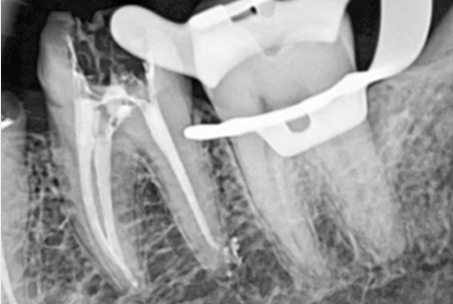

위 사진들은 현직 치과의사들이

저희 웃는얼굴 치과에서 치료 받은 실제 사례들입니다.

비 전문가 눈에는 그냥 흔한 엑스레이 사진일 뿐이겠지만

치과의사들이라면 알아챕니다.

저 치료가 얼마나 난이도 있는 치료였는지,

얼마나 정성이 들어갔는지를 말이지요.